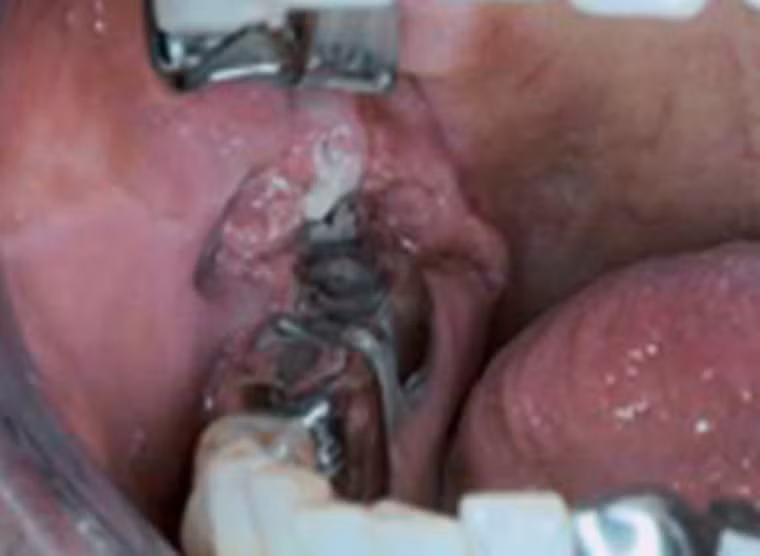

Nghiêm trọng hơn, người đàn ông này bị mắc ung thư biểu mô tế bào vảy dạng nhú. Khối u có màu trắng, gây lở loét. Nguyên nhân chính của căn bệnh cũng bắt nguồn từ thói quen hút thuốc lá.